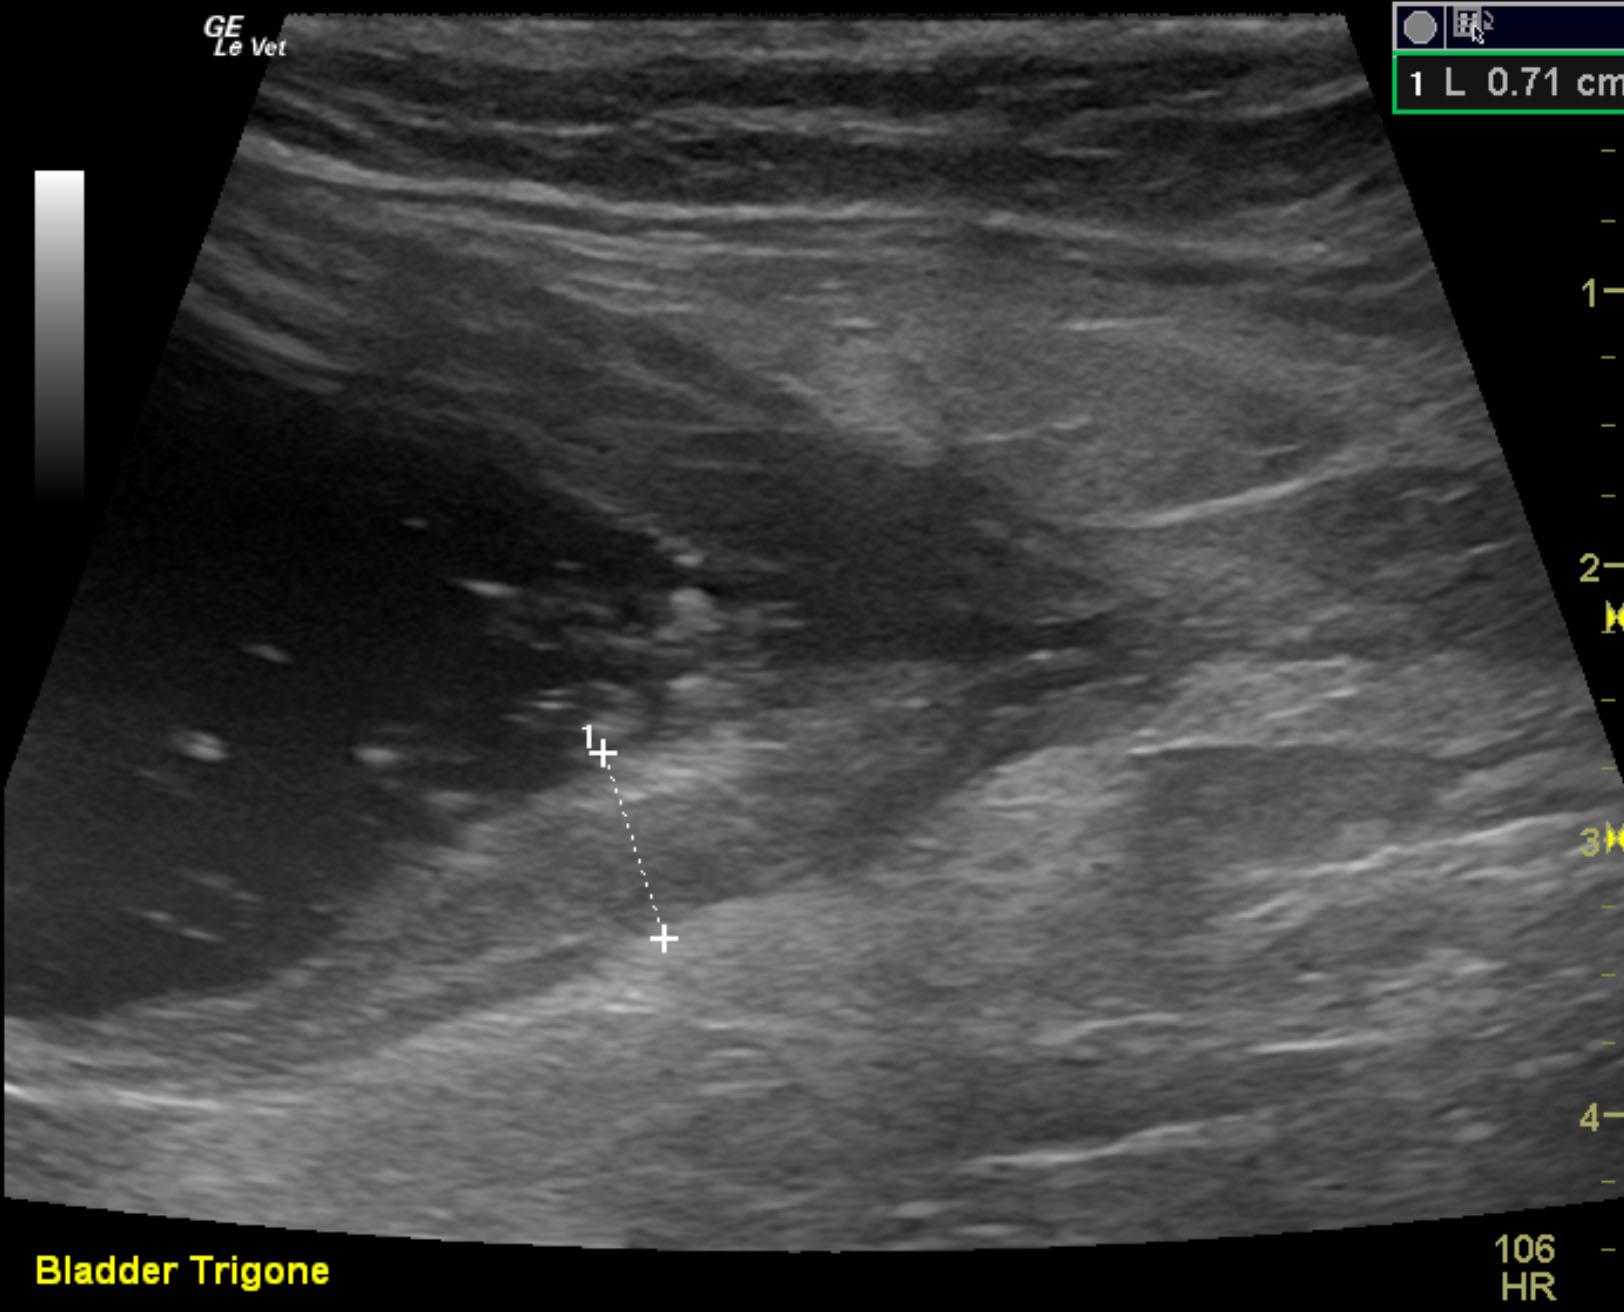

A 2-year-old neutered male DMH cat was presented for urethral obstruction and a possible mass dorsal to the urinary bladder. The cat also had a 5-day duration of diarrhea.